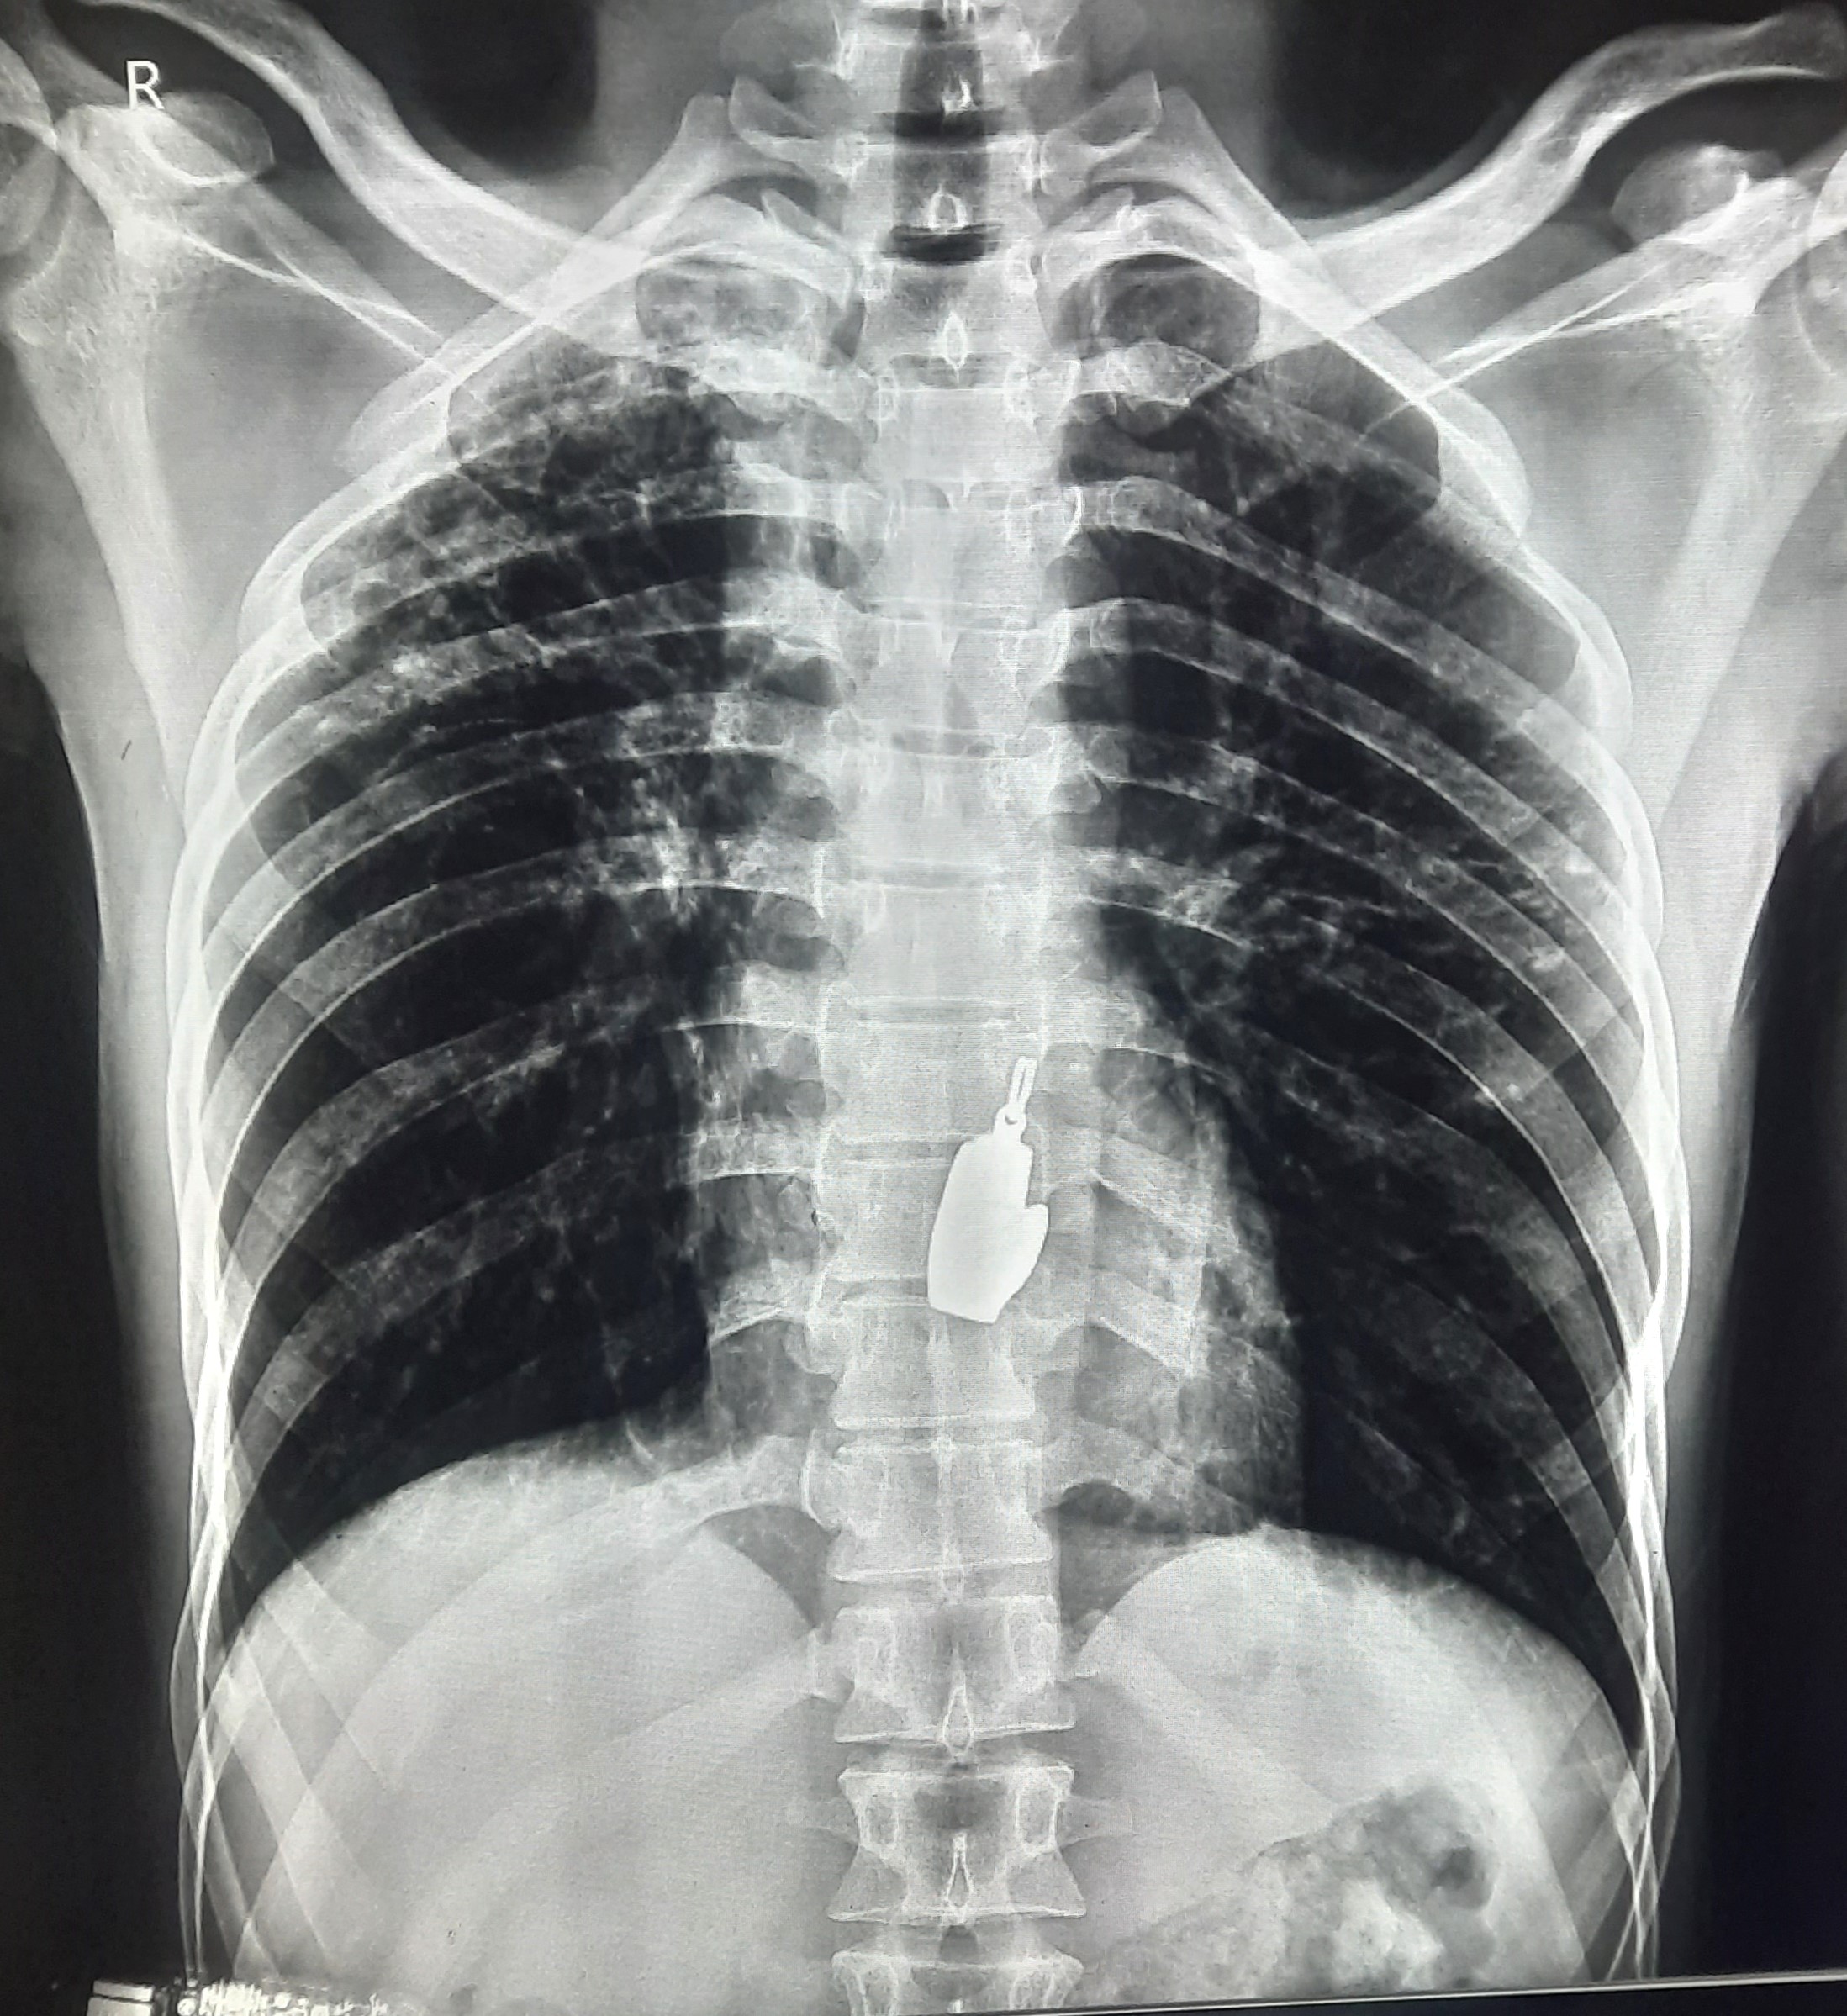

| 84 | IGGMC, Nagpur, Nagpur | P2 | 29-4388 | Dipak Panchbudhe | Consent taken on Paper | 33 Yrs. |

Provisional Diag : Pulmonary Tuberculosis Reactivation ?

Final Diag : Pulmonary Tuberculosis |

TB Case (Confirmed) | Bilateral multiple ill-defined alveolar opacity present, Left Sided Upper Zone Fibro Cavitary Lesion Present | Abnormality visible on x-ray |